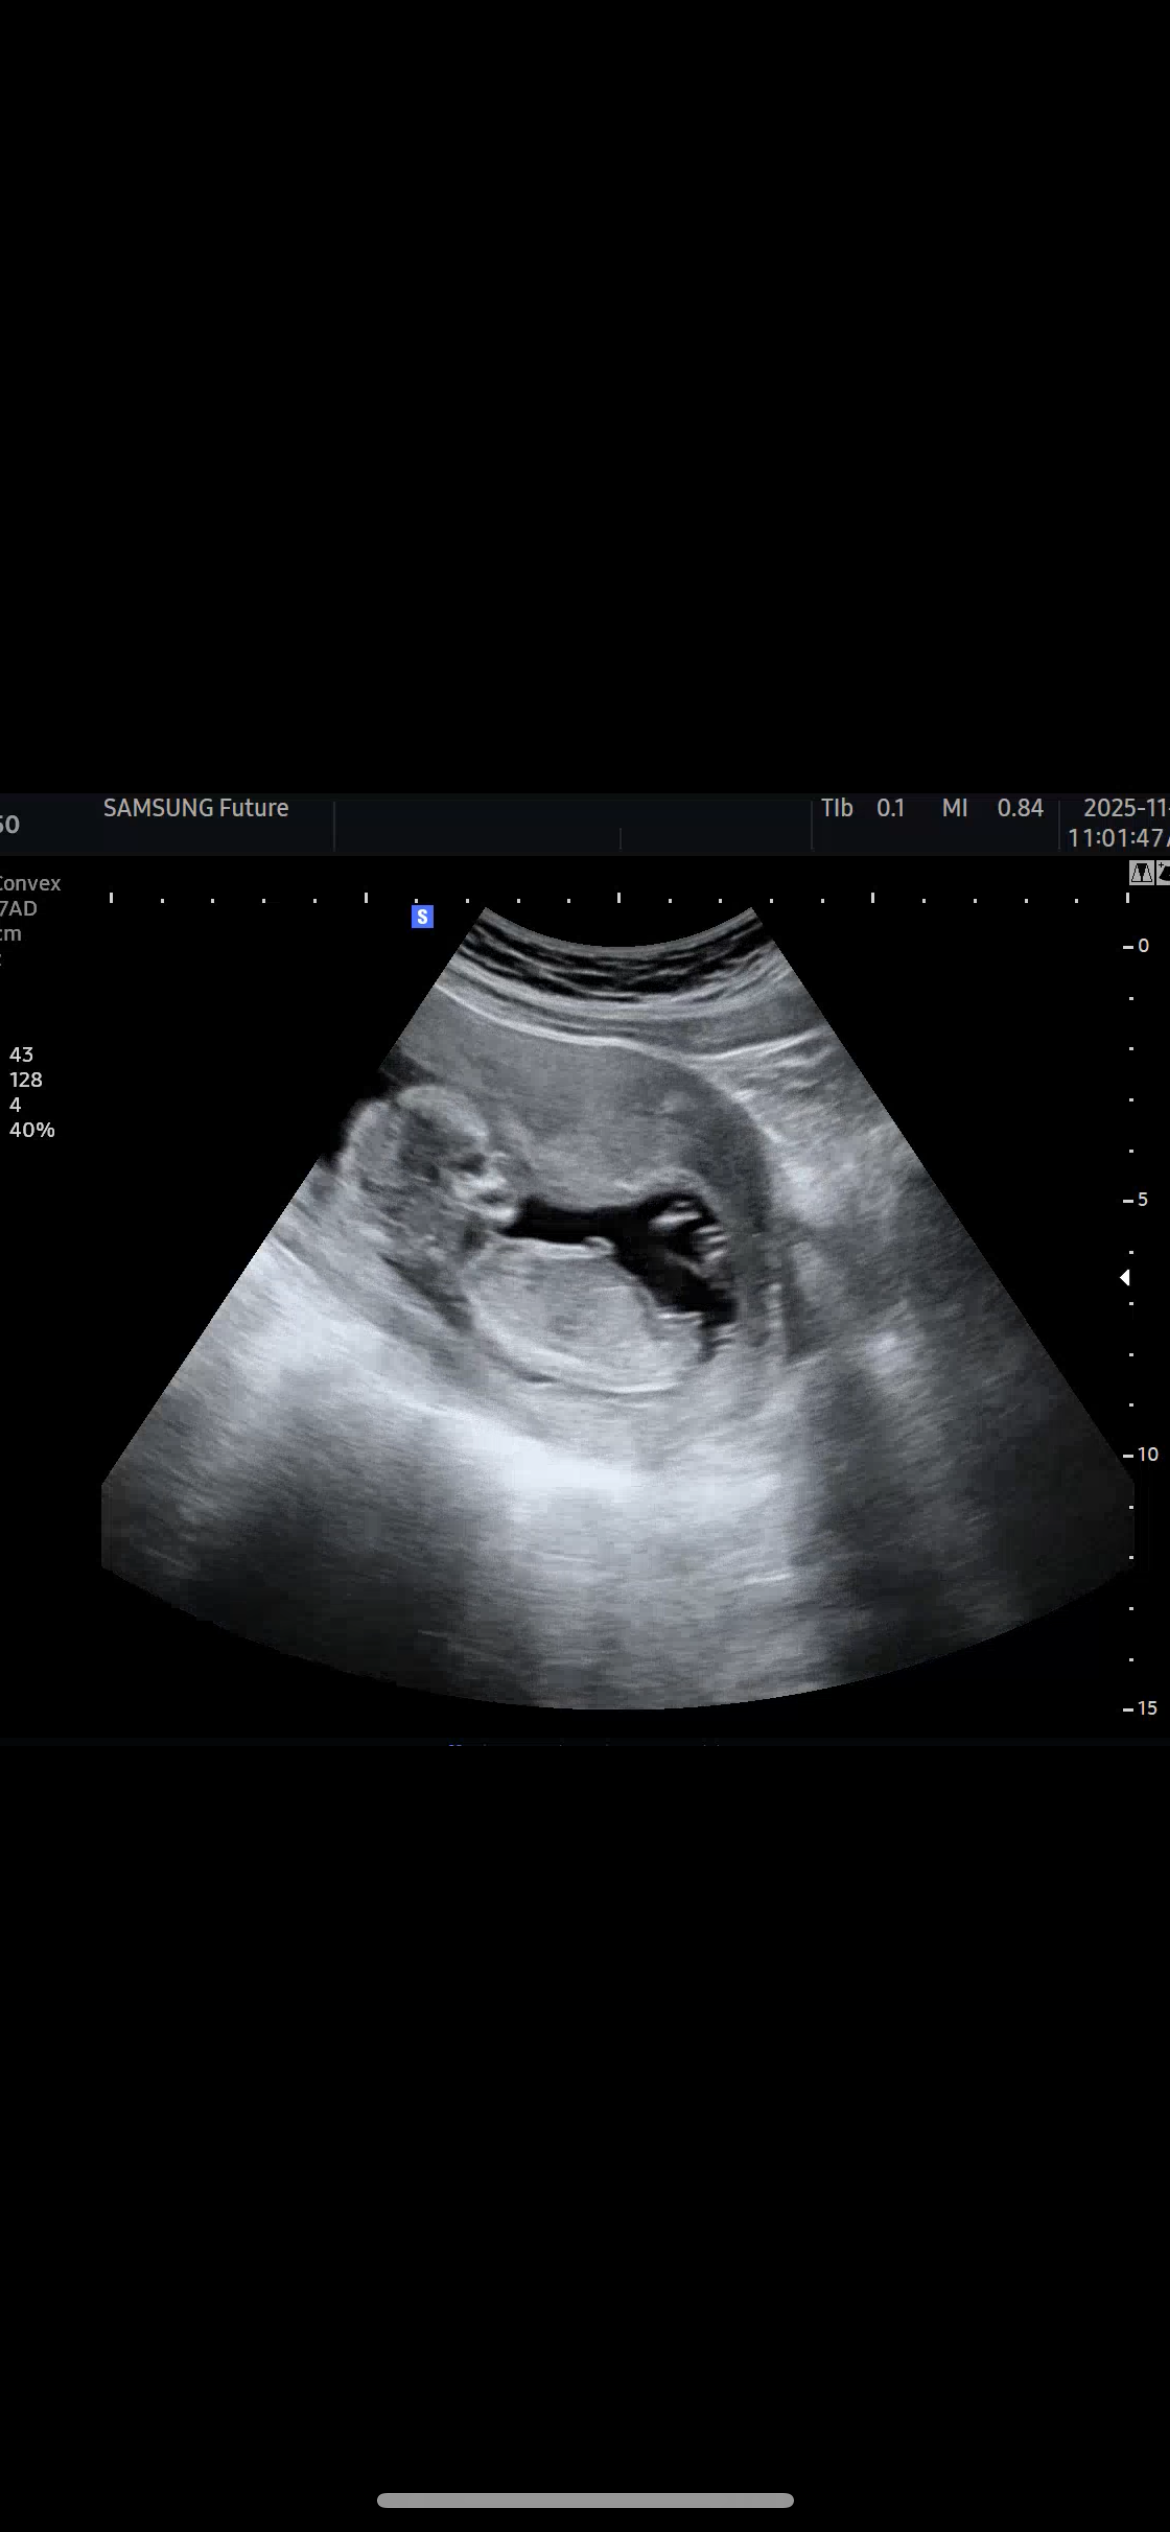

남편 삼형제 시아버님 삼형제 시사촌들 싹다 남자집인 시댁에서 딸을 낳고 혁명을 일으키겠다는 새댁입니다. 저희 외갓댁은 딸 성비가 더 커서 딸 가능성 있다고 희망을 말해도 남편은 무조건 아들일거라고 자기집 유전자 세다고 계속 아들라이팅 해서 산모교실 이런데 가서 선물 싹다 파란걸로 받아왔거든요 ㅋㅋㅋㅋㅋㅋㅋ 근데 오늘 14주차 병원에서 촘피 봤는데 제 느낌엔 아무래도 딸같아요…각도법이… 빌리 ai 판독기 돌려봐도 딸 나오구요…. 고수님들 소중한 투표 한번만 꾸욱 부탁드려요🥹👍💗 고수 아니어도 돼요 그냥 눌러주세여….

저 12주때 사진이랑 비슷한거같아요! 얼핏 아들각도인데 등이 구부러져있어서 딸같기도??!! 주변 모두가 아들각도라고 했지만 어제 16주 초음파 보고왔는데 대반전으로 딸이었어용!!!!ㅋㅋㅋ 원하는 결과 있으시길 바래요!!!

엇 그러게요! 저랑 성기각도가 매우 비슷하네욤,,,, 2주 기다려야 16주 2차 기형아 검진 때 알수 있을 것 같은데ㅠㅠㅠ 어떻게 기다리죠,,,,ㅋㅋㅋㅋㅋㅋㅋㅋ 후기 답글로 알려드릴게요!!

안녕하세요!! 저 16주 3일에 딸이라고 확인받고 나왔어용~~~ 다리사이가 아주 매끈매끈하네용ㅋㅎㅎㅎ